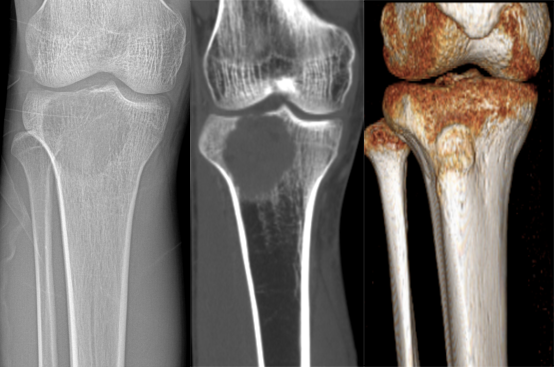

CASE 1男性,23 岁,主诉:右小腿上段疼痛伴右膝关节肿胀 2 月余

378e3adfddcb4fd88a7dac9006626939.png

f0c75cbf4ac005bdf44c1a191c0ff29c.png

免疫组化结果:右胫骨肿瘤,骨巨细胞瘤。